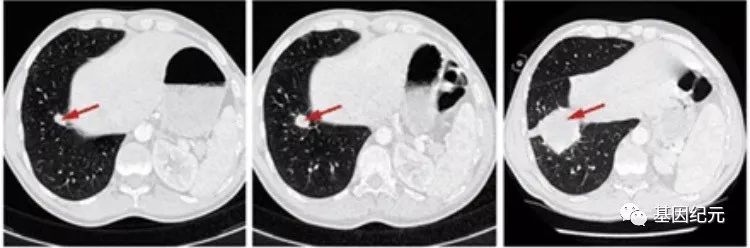

两年多的时间过去了,由于越来越多的类似临床病例的出现,使得癌症过快进展的问题受到进一步的关注。最近一期[科学]杂志发表了一篇文章,题目为:“肿瘤免疫治疗也可能有黑暗的一面”(Cancer immunotherapy may have a dark side),对这一问题专门做了评述。文章还列举了一个病例。是位65岁患有一种罕见子宫内膜癌的女性患者,在加州大学圣地亚哥分校(UCSD)肿瘤科接受治疗。患者癌症已经扩散到肝脏,显然预后非常不好,但她本人仍然感觉不错,能够胜任工作和游泳。作为最后的希望,医生给她用了PD-1免疫药物。虽然这种药物可能在其他晚期癌症患者中有奇迹般的效果。但是,当她开始用药的3周后,腹部迅速肿胀,肝脏肿瘤已经迅速增大到像柑橘一样大小(图)。医生说:“她刚刚出现了肿瘤爆发式增长,虽然无论如何她都会死去,不幸的我们可能加快了她的死亡。”

患者PD-1治疗前肿瘤体积不是很大(左图); PD-1治疗3周后肿瘤快速长大(右图)